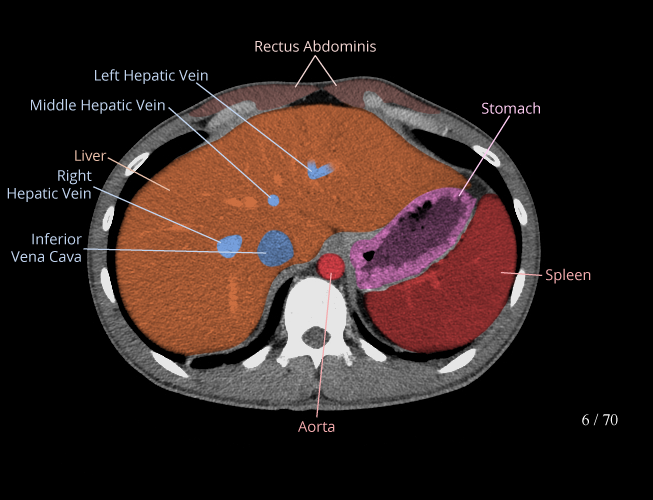

Body

Covers abdominal CT anatomy.